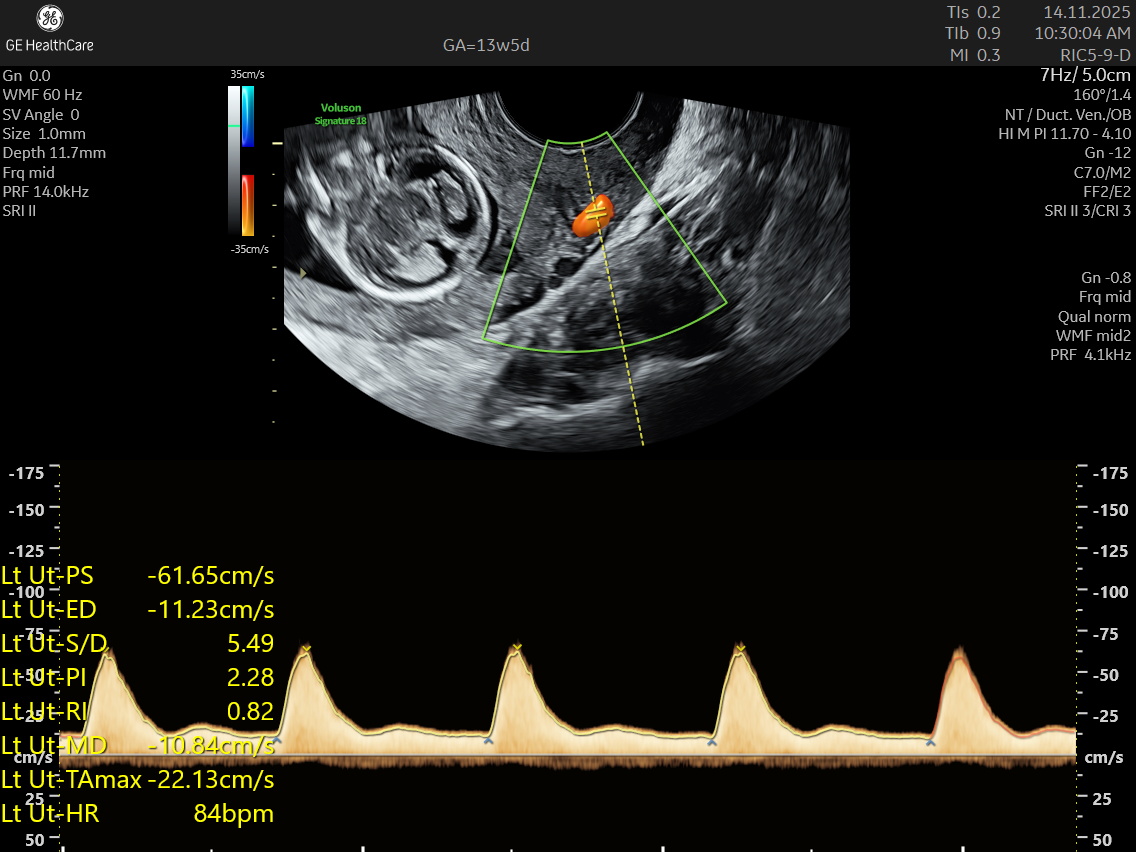

NESA Institute of Fetal Medicine offers specialized first-trimester screening for expectant parents, delivering high-precision NT scans between 12 to 13 weeks of pregnancy. Our experienced fetal medicine team ensures accurate risk assessment for chromosomal abnormalities, including Down syndrome, Edwards syndrome, and Patau syndrome.

The NT scan is a non-invasive ultrasound examination conducted in the first trimester (12–13 weeks). It measures the nuchal translucency (the fluid at the back of the fetus’s neck) and combines it with the maternal blood test for a detailed risk profile. NT Scan is an important early screening test for Down syndrome (Trisomy 21), Edwards syndrome (Trisomy 18), and Patau syndrome (Trisomy 13).

Although the NT scan is mainly a screening tool and not diagnostic on its own, it can identify about 50% of major fetal abnormalities when combined with other assessments like blood tests and detailed ultrasound. The scan also helps to screen some basic anatomical structures during the first trimester, especially the fetal heart anatomy, brain, face, spine, stomach, abdominal wall, kidneys, bladder, and extremities to varying degrees depending on gestational age and maternal factors.